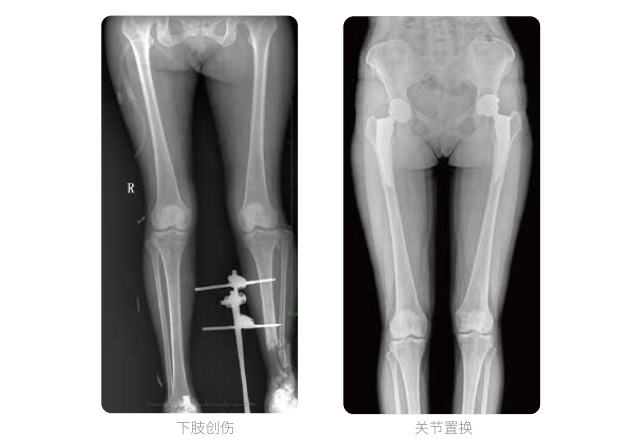

雙下肢臨床影像

髓內(nèi)釘手術(shù)是骨科、手足外科中常見的微創(chuàng)型手術(shù)方式,患者隨訪時(shí)需拍攝置入在股骨、肱骨處的較長(zhǎng)髓內(nèi)釘。PLX8600視野拍攝,能夠出色解決醫(yī)生需多次攝影再拼接的痛點(diǎn)。一次成像雙下肢,即拍即得,高效率,無需拼接。工作站軟件自帶的測(cè)量功能方便醫(yī)生讀取雙下肢長(zhǎng)度數(shù)據(jù),助力準(zhǔn)確診斷。